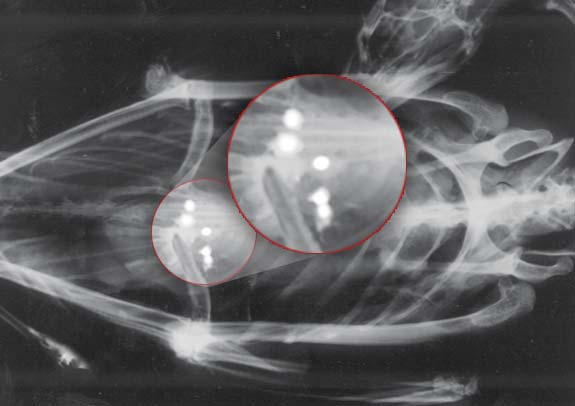

Loons pick up small pebbles from lake bottoms to help grind their food. Unfortunately, lost or discarded lead sinkers and jigs are very similar in size and shape to the grit they naturally ingest. Once swallowed, the lead is quickly ground down in the loon’s gizzard and absorbed into the bloodstream.

A Wisconsin review of loon deaths found that about 30% of loons submitted for necropsy died of lead poisoning; in every confirmed case, remnants of lead tackle were found in the bird’s digestive tract.